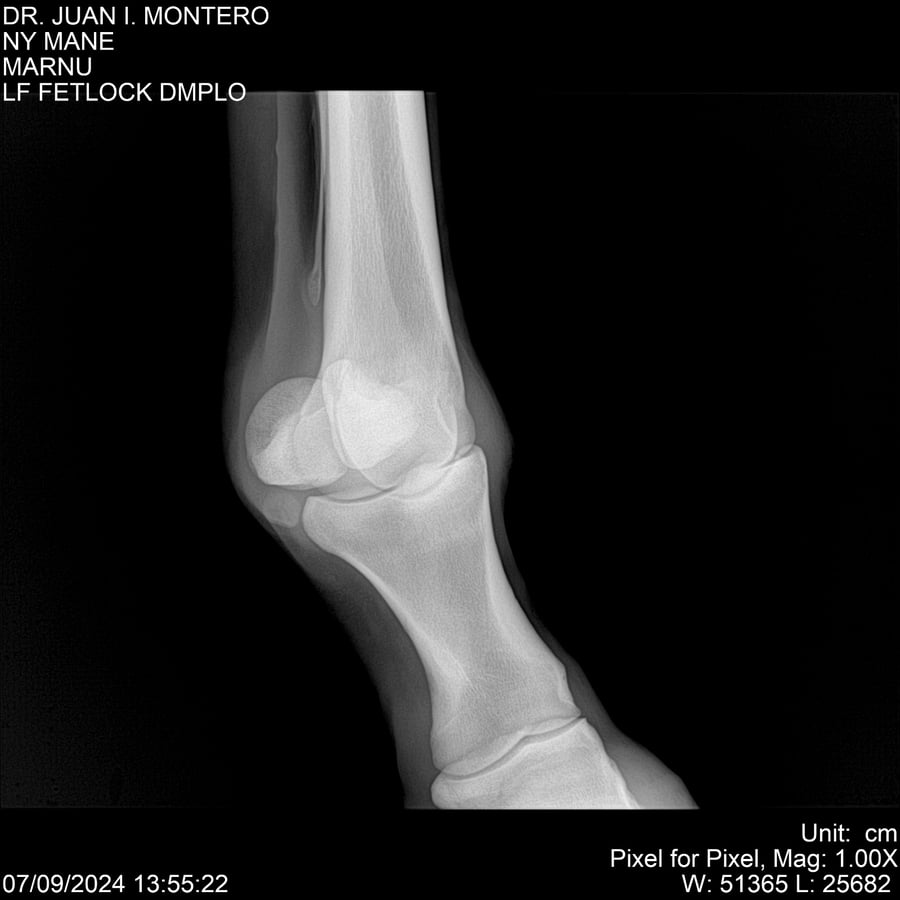

LOTE 20, NY MANE Lote Anterior Volver al remate Lote Siguiente Ficha Contacto Montevideo - Ficha del Lote Identificador: #282520 Categoría: Yeguarizos 76 Visualizaciones ClicData Contacto Empresa: Abelenda N. R., Walter Hugo Nombre*: Teléfono* : E-mail* : Mensaje Enviar Registrese gratis Este contenido Exclusivo está disponible sólo para usuarios registrados Ingresar